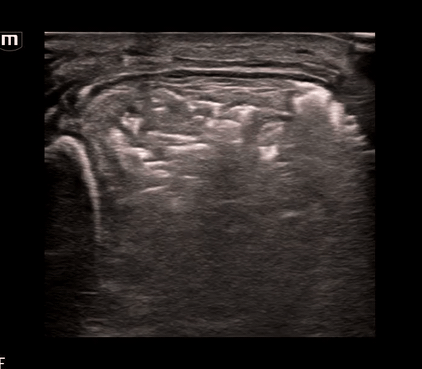

Using the linear probe for better visualization of superficial structure, let’s take a look at what we saw on the left lower leg:

What do we see?? Air and “dirty shadowing” in the soft tissue concerning for necrotizing fasciitis in this clinical context.

We can identify necrotizing fasciitis on US by using the acronym “STAFF”

• S – Subcutaneous thickening: diffuse thickening and distortment of soft tissue layers seen

• T – Thickened fascia:  chunky fascia not a thin bright white line

• A – Air: posterior dirty acoustic shadowing, corresponding to gas in the soft tissue

• F – Fascial fluid: Anechoic fluid collections (<2mm)